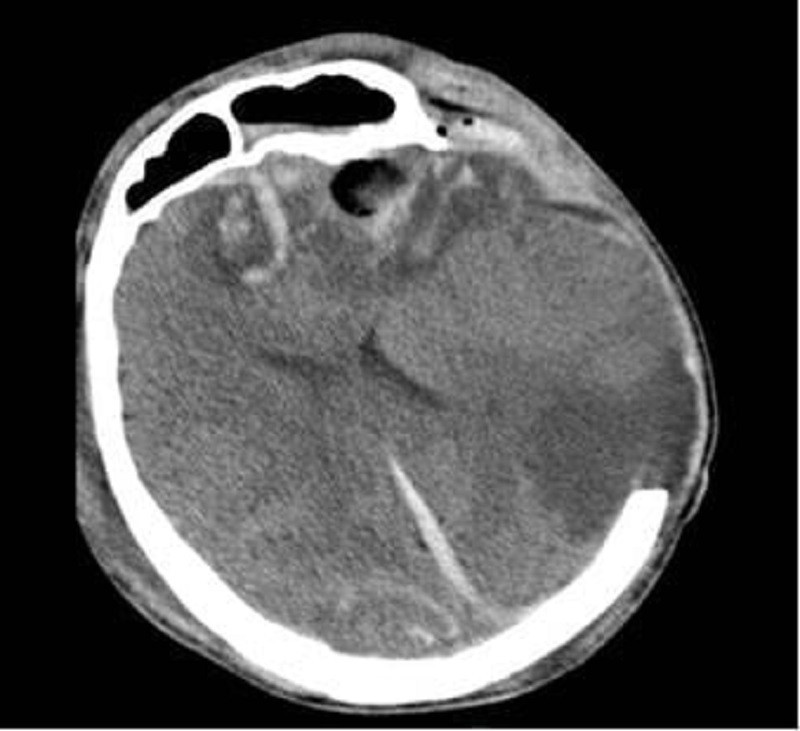

BS Dũng cho biết, người con trai G.A. (28 tuổi) nhập viện trong tình trạng hôn mê sâu, phải thở máy qua nội khí quản. Kết quả CT scan sọ não ghi nhận dập não xuất huyết rải rác nhiều vị trí, phù não lan tỏa nặng dù đã được mở sọ giải ép tối đa. Đây là dạng chấn thương sọ não rất nặng, diễn tiến khó lường, nguy cơ tử vong luôn ở mức cao. Người bệnh được điều trị tích cực tại Đơn vị Hồi sức Ngoại khoa, khoa Gây mê Hồi sức, với sự theo dõi sát các chỉ số sinh tồn và áp lực nội sọ.

Phim CT não người bệnh G.A. cho thấy dập não xuất huyết nhiều nơi, phù não lan tỏa dù đã được mở sọ giải ép (ảnh: BVCC)

Cùng thời điểm đó, mẹ của anh là bà G.N. (53 tuổi) cũng được chuyển đến Bệnh viện Nhân dân 115 trong tình trạng lơ mơ. Hình ảnh CT scan cho thấy dập não thái dương với ổ xuất huyết lớn kèm phù não xung quanh. Sau khi hội chẩn kỹ lưỡng, các bác sĩ quyết định lựa chọn phương án điều trị bảo tồn thay vì phẫu thuật nhằm hạn chế tổn thương não thứ phát. Sau nỗ lực điều trị của các bác sĩ khoa Ngoại Thần kinh, sức khỏe bà G.N. đã hồi phục tốt.